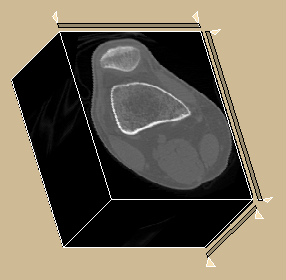

Second, given that the 3D extension of ISF simply requires a different choice of adjacency relation, we present a comparison between the best ISF method for this application (ISF-GRID-MEAN with ), the only baseline with 3D implementation (SLIC), and the hybrid approach (SLIC-ISF) on volumetric MR images of the brain. In this dataset, there are three objects of interest: cerebellum, left and right brain hemispheres (Figure 8a). Segmentation creates supervoxels as shown in Figure 8b. Supervoxels with more than 50% of their voxels inside a particular object are labeled as belonging to that object, otherwise they are considered as part of the background or other objects. Effectiveness is measured by f-score for three supervoxel resolutions, given the usual image sizes: low (), medium (), and high (). Table I shows the results of this experiment, using a 64 bit, Core(TM) i7-3770K Intel(R) PC with CPU speed of 3.50GHz. It is not a surprise that ISF outperforms SLIC in effectiveness. However, SLIC is exploiting parallel computing 444Without parallel computing, SLIC would take from 19s-23s of processing time for to supervoxels. and given that SLIC-ISF is twice faster than ISF, their equivalence in performance above medium superpixel resolution is an excellent result. Another interesting observation is that ISF performs better for a value of () lower than (i.e., more regular supervoxels).

Figures 8c-d show another example using ISF-GRID-MEAN, where the specification of 10 supervoxels using segments the patella bone as one of the supervoxels.